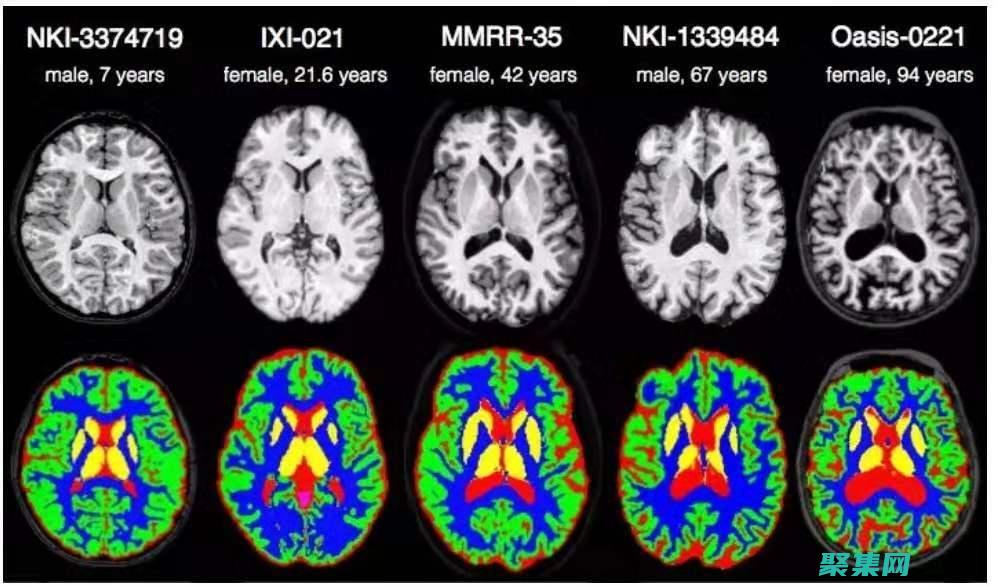

• MRI 掃描:圖像處理可以增強 MRI 掃描圖像的對比度,使組織和病變更容易識別。